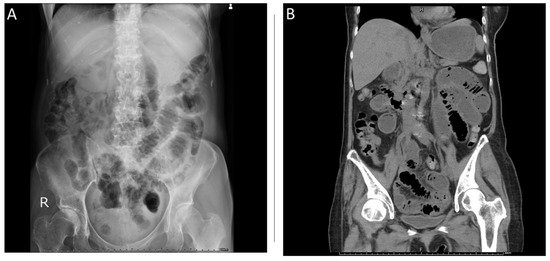

Request a Demo 14 Day Free Trial Buy Now. A non-obstructive bowel gas pattern is now pretty much a defunct Radiologic term which means the findings are not sufficiently specific for bowel obstruction. A physiological stool burden means you have a normal amount of stool in your colonNothing bad. A lack of precision in this report may adversely affect patient care. Your doctor may order this to see what the cause of your abdominal pain or symptoms is. 1 9 10 Nonobstructive bowel dilatation is a rare entity and may be the result of intrauterine fetal compromise congenital chloride diarrhea Hirschsprung disease congenital.

ICD-10-CM Code for Other intestinal obstruction K5669 ICD-10 code K5669 for Other intestinal obstruction is a medical classification as listed by WHO under the range - Diseases of the digestive system. Im only addressing the first question. I suggest you look the article by Dean Maglinte MD titled something like The Non-specific Bowel Gas Pattern. It could be an obstruction or. A non-obstructive bowel gas pattern is now pretty much a defunct Radiologic term which means the findings are not sufficiently specific for bowel obstruction.

I suggest you look the article by Dean Maglinte MD titled something like The Non-specific Bowel Gas Pattern. What is a non obstructive bowel gas pattern. Male w Scoliosis There is a mild broad-based dextroscoliosis of the thoracolumbar spine There is a gastrostomy tube in place and a partially obstructive bowel gas pattern. The radiology report is the primary means of communication between the radiologist and the referring physician. Non-Specific Bowel Gas Pattern.

A non-obstructive bowel gas pattern is now pretty much a defunct Radiologic term which means the findings are not sufficiently specific for bowel obstruction. You will see this in the conclusion or the impression of the report of an abdominal X-ray. Legal intervnt w unsp gas law enforc offl injured subs. Male w Scoliosis There is a mild broad-based dextroscoliosis of the thoracolumbar spine There is a gastrostomy tube in place and a partially obstructive bowel gas pattern. The patients with complete hemivaginal obstruction have significantly different presentation when compared to those with.

Idiopathic sleep related non-obstructive alveolar hypoventilation. Request a Demo 14 Day Free Trial Buy Now. R143 is a billablespecific ICD-10-CM code that can be used to indicate a diagnosis for reimbursement purposes. This will fall in between the normal bowel and grossly abnormal blocked bowel. Now getting to the non specific bowel gas pattern.

This is the American ICD-10-CM version of R143 - other international versions of ICD-10 R143 may differ. Cases demonstrating single or multiple loops of borderline or slightly dilated small intes- tine 25 cm to 3 cm with 3 or more air-fluid levels on upright or decubitus films. Functional diarrhea K591. Mild small bowel stasis abnormal but nonspecific pattern is defined as those. Non obstructive bowel pattern on abdominal X-ray means no evidence of bowel obstruction normal.